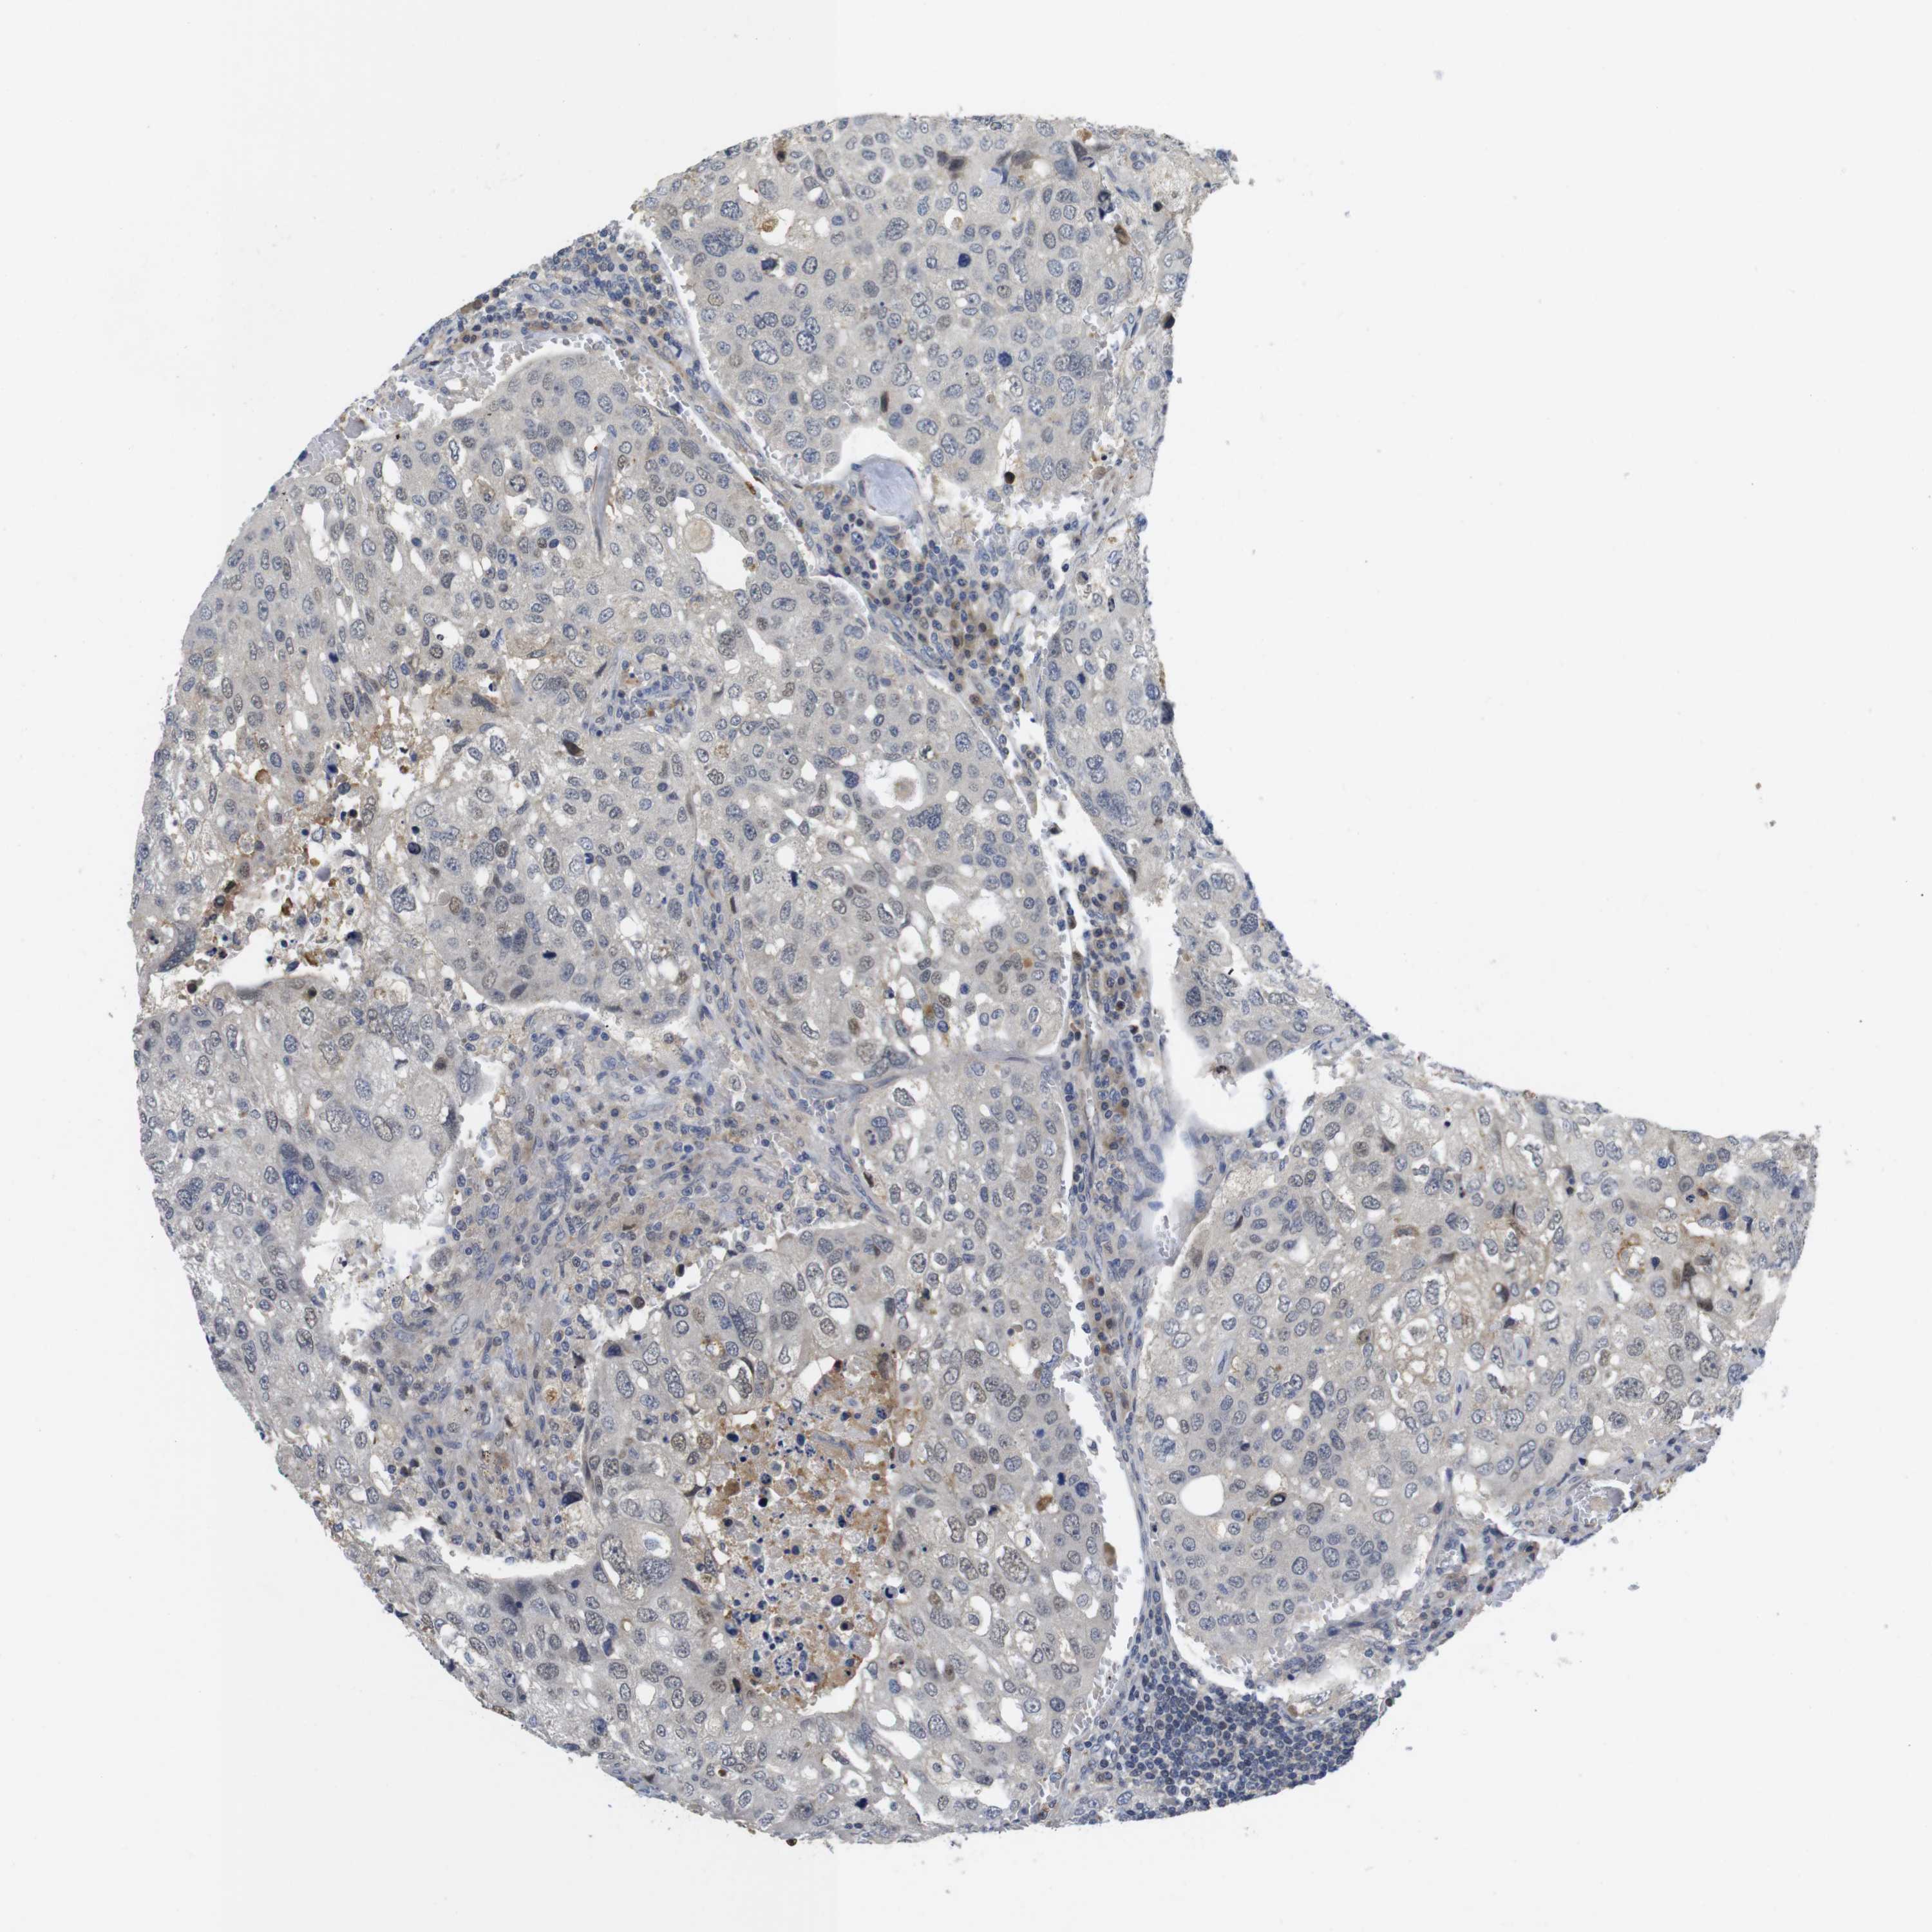

UROTHELIAL CANCER - Protein expressioni

A mouse-over function shows sample information and annotation data. Click on an image to view it in a full screen mode. Samples can be filtered based on level of antibody staining by selecting one or several of the following categories: high, medium, low and not detected. The assay and annotation is described here.

Antibody stainingi

Antibody staining in the annotated cell types in the current human tissue is reported as not detected, low, medium, or high, based on conventional immunohistochemistry profiling in selected tissues. This score is based on the combination of the staining intensity and fraction of stained cells.

Each image is clickable and will lead to virtual microscopy that enables deeper exploration of all samples and also displays staining intensity scores, fraction scores and subcellular localization as well as patient and tissue information for each sample.

Antibody HPA018830

Antibody CAB010149

Urothelial carcinoma, Low grade

Urothelial carcinoma, High grade